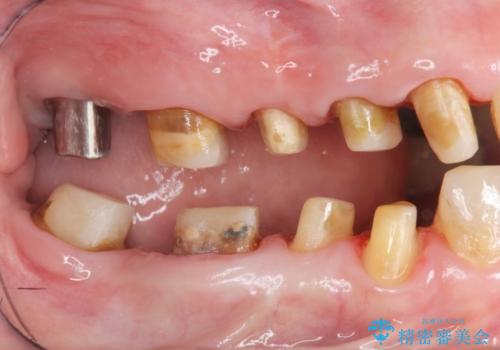

- 見た目の悪い銀歯や虫歯、歯の欠損、全体的な治療を希望されて来院されました。

インプラント治療や根管治療・セラミック治療を総合的に考えた精度の高い治療を計画し、しっかり噛めるようになるのはもちろん長期的な予後や審美性の向上を考えた全顎的な治療を実践していきます。